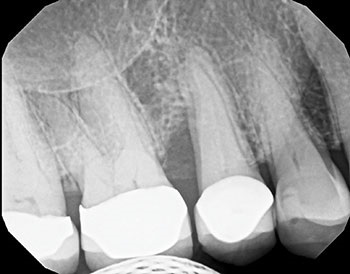

An initial clinical exam revealed an 8 mm periodontal pocket depth on the distal of maxillary #13. The presence of slight bleeding and purulence was evident during periodontal probing. A periapical X-ray showed a loss of epithelial attachment and pocketing, which led to endodontic involvement in tooth #13 (Figs. 1 and 2). The tooth also exhibited early grade 2 mobility. Contributing factors included pain on vertical percussion, indicating primary periodontal with secondary endodontic involvement.

Fig. 1: Pre-operative X-ray.